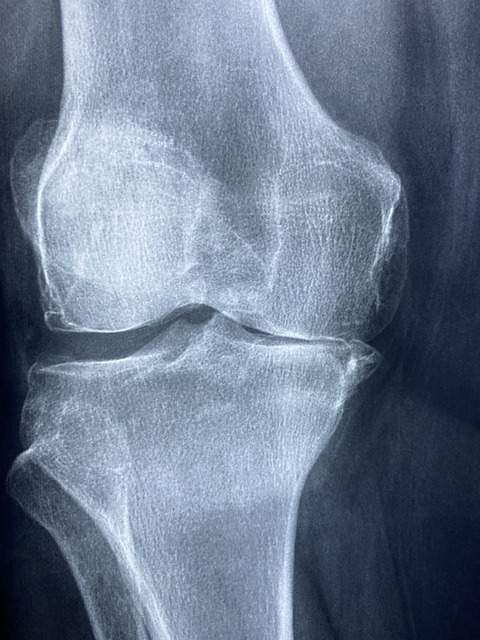

무릎 인공관절 수술은 퇴행성 관절염이나 심각한 관절 손상을 겪는 환자들에게 효과적인 치료법입니다.